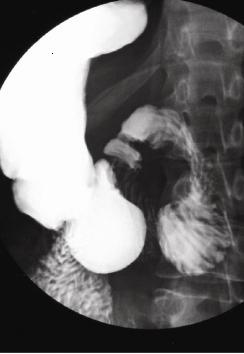

| images TOGD de oesophage

normale |

image TOGD de oesophage (

angle de His ) et estomac normale |